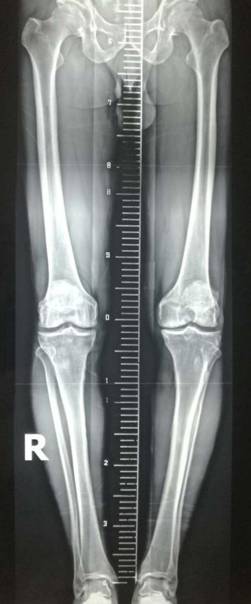

全膝表面置换术治疗重度骨关节病

优点:疗效可靠,膝关节病的最终解决方案。

术前术后对比

全膝关节翻修术

全髋关节翻修术